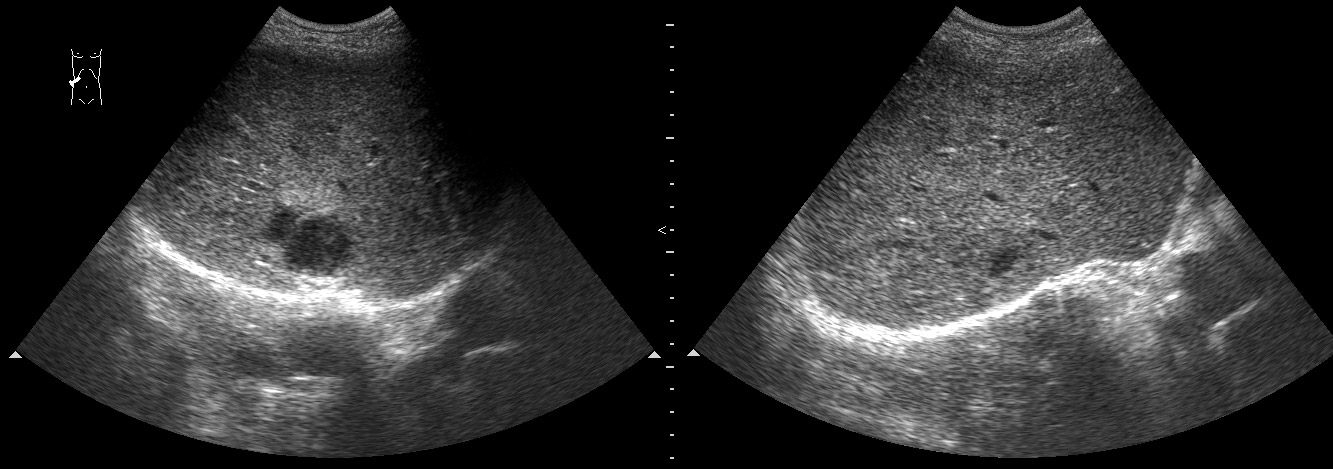

#6

Пожилой мужчина, мы ему уже дренировали абсцесс левой доли печени как минимум полгода назад.

Опять температура, симптомы интоксикации.

В левой доле определяется один крупный и несколько мелких абсцессов.

Больший абсцесс задренирован, мелкие раздренировались самостоятельно в бОльший.

У него же, по-видимому, мелкие протоковые конкрменты: